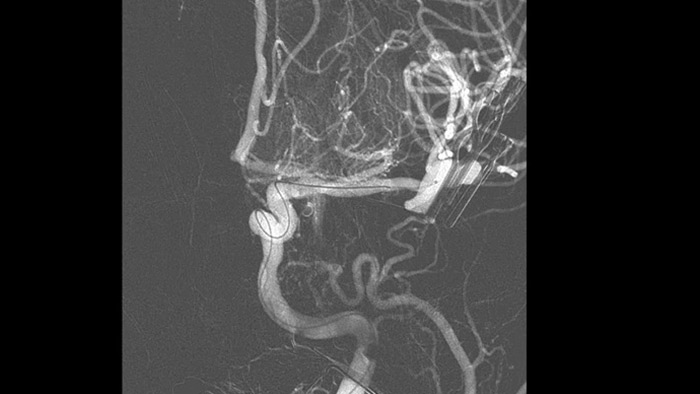

Visualisation d’angiographie par soustraction numérique (ASN)

Les visualisations d’angiographie par soustraction numérique (ASN) de haute qualité vous permettent d’évaluer si vous avez retiré le caillot complet et si des morceaux de caillot ont été dispersés de manière distale dans le cerveau. Vous pouvez vérifier le rétablissement du débit sanguin dans la pénombre et contrôler les hémorragies péri-procédurales.